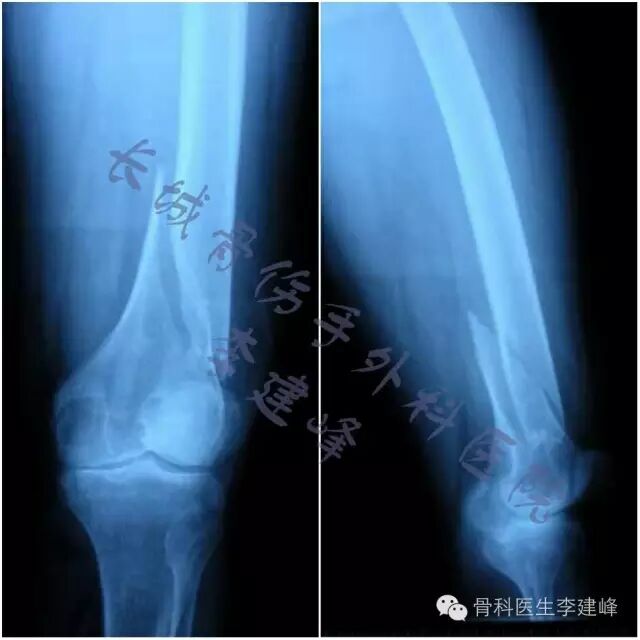

Three case :

术前